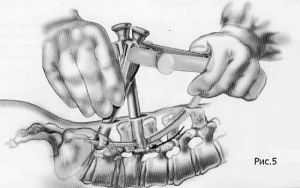

Хирургическое лечение спондилолистеза заключается в фиксации «разболтанных» позвонков титановыми винтами. Винты вводятся в позвонки через дужки позвонков (с лат. «педикули»), поэтому такая фиксация называется «транспедикулярной». Данный метод фиксации позвонков был впервые применен Roy-Camille в 1963г. и используется благодаря своей высокой эффективности по всему миру до настоящих дней.

Кроме того, в зависимости от техники проведения операции могут использоваться межтеловые кейджи. Кейдж (в переводе с английского «cage» означает «сетка») представляет собой титановый или пластиковый имплант, заполняемый собственной костной крошкой пациента или другим остеоиндуктивным (костьобразующим) материалом. Кейджи устанавливаются в полость диска, в результате чего восстанавливается высота последнего и соответственно высота фораминального отверстия (через который выходит спинномозговой корешок из позвоночного канала). Кейджи могут быть цилиндрической или прямоугольной формы, выполненными из титана или «PEEK»-керамики. Титановые цилиндрические кейджи в настоящее время используются редко.

Наиболее современным методом фиксации в настоящий момент является миниинвазивная технология введения винтов через небольшие разрезы. Этот метод позволяет меньше травмировать мышцы разгибатели позвоночника при введении винтов, а также более быстрому выздоровлению пациента и возвращению к обычному образу жизни, активному отдыху и работе. Технология данной фиксации заключается в использовании канюлированных винтов, т.е. винтов с отверстием в центре. В начале в тело позвонка вводится спица, а уже по спице вводится винт. Удаление грыжи диска и введение кейджа в межтеловой промежуток производится через тот же разрез, что и введение винтов.